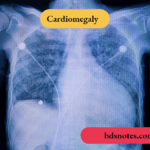

Massive Cardiomegaly: Causes and Underlying Cardiac Conditions

Massive Cardiomegaly: Causes and Underlying Cardiac Conditions Question. Enumerate the causes of massive cardiomegaly. Answer. The causes of massive cardiomegaly are: Hypertrophic cardiomyopathy and dilated *cardiomyopathy Congenital insuffiency of tricuspid valve Pediatric anesthesia Nonuniform pulmonary artery perfusion Idiopathic arterial calcifiation … [Read more...] about Massive Cardiomegaly: Causes and Underlying Cardiac Conditions